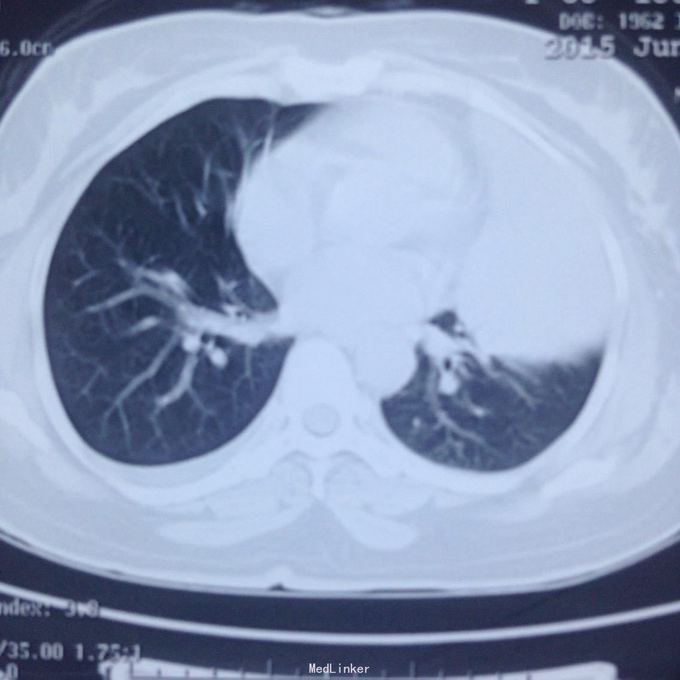

主诉:发现胸腔积液4月余。 现病史:患者4个月前因腰椎间盘突出在当地医院就诊,检查发现双侧少量胸腔积液,量不多,2个月后胸闷气短再次在当地医院复查胸部ct,提示双侧胸腔积液较前增多,左侧明显。

左侧胸腔包裹性积液? 完善胸腔b超提示左侧胸腔包裹性积液,最深处约59mm,内透声较差。予以定位后诊断性穿刺未抽出明显液体,当时考虑液体可能较粘稠或包裹分隔,遂决定予以小切口开胸探查。开胸后见胸腔积液,量约300ml,颜色较清亮,予以抽吸后在探查,见脏层及壁层胸膜无增厚及明显粘连,遂考虑不排除囊肿可能性,继续探查见胸膜顶靠近左纵隔处一囊壁,已破裂,囊壁挛缩成团,予以切除,术后病检为胸腺囊肿。

术后病检为胸腺囊肿。术后讨论:患者多次胸部ct均提示为包裹性积液,因囊肿较大,囊壁较薄,且靠近胸壁,易误诊为包裹性积液,但患者一直无发热病史,且复查ct积液位置靠胸前壁,术前应该考虑到囊肿可能,因患者经济较困难,至本院后未行增强ct,穿刺后考虑穿刺针将囊壁穿破,故开胸后未见完整囊肿,此类看似简单的病例容易由其他医院诊断误导,并且容易误诊。